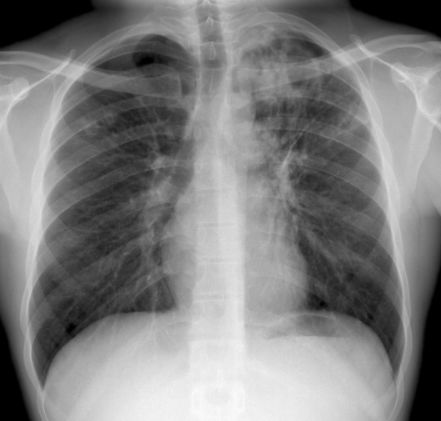

今年的3月24日是第25个世界防治结核病日,我国的宣传主题是“携手抗疫防痨、守护健康呼吸”。据世界卫生组织统计,每天有超过4000人死于结核病,并有近3万人感染这种可预防且可治愈的疾病。而我国是全球30个结核病高负担国家之一,位居全球第2位,每年新报告肺结核患者约80万例,位居甲乙类传染病第2位。

(图源:123RF)